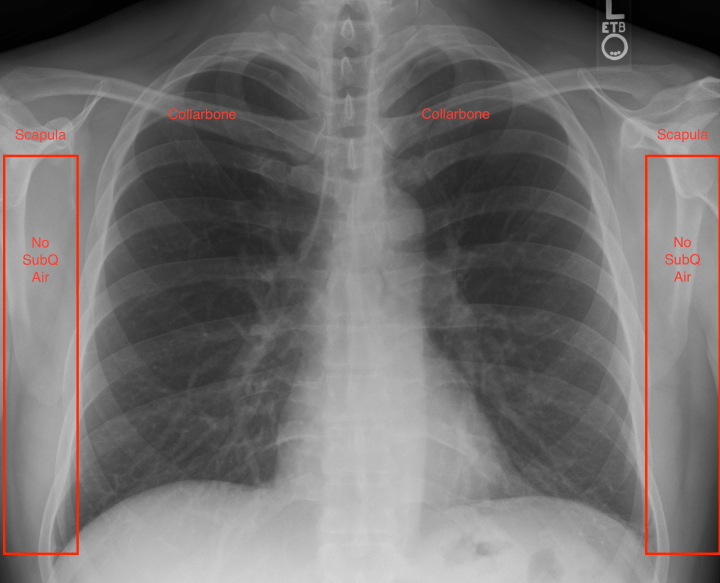

- Subcutaneous Air: While 99% of people might believe X-rays only demonstrate changes in boney structures, 100% of them would be wrong. A lot of information can be elucidated from the surrounding soft tissues. To begin, examine the soft tissues of the axilla & chest walls. ZERO air pockets or ‘bubbles’ should be seen. Any indication of such would imply air escaped from the thorax and a pneumothorax just jumped to the top of your differential.

- Peripheral Bones: Portions of both humerus, scapula and shoulder joints should be visible on CXRs. Additionally, both collarbones should be clearly seen. Take 2 seconds to compare them bilaterally to convince yourself you didn’t miss an embarrassingly obvious fracture or dislocated shoulder which could easily be masked by another more distressing patient complaint.